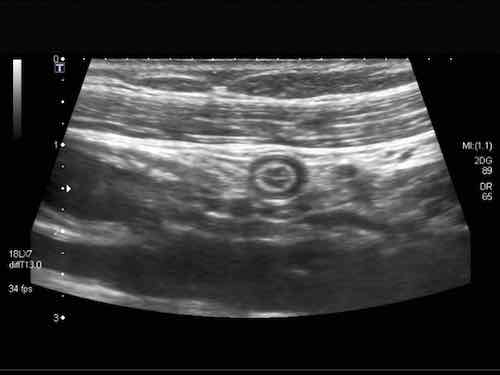

Đây là hình ảnh siêu âm của một trẻ 2 tuổi bị lồng ruột hồi manh tràng từng đợt, được khám trong khoảng thời gian giữa các cơn.

Hồi tràng với nhiều mảng Peyer sa vào manh tràng.

Hình ảnh siêu âm kinh điển của lồng ruột hồi-manh tràng ở hai trẻ khác nhau.

Trong cả hai trường hợp, đoạn hồi tràng bị lồng được định vị không đối xứng bên trong ống lồng ngoài, do mạc treo ruột tăng âm có chứa mỡ, bám vào hồi tràng và đi theo hồi tràng khi bị kéo vào trong.

Trong mạc treo, siêu âm cho thấy một hạch bạch huyết mạc treo (hbh) phóng đại ở cả hai.

Các hạch này phì đại như một phần của tình trạng tăng sản hạch bạch huyết toàn thân và khônghu trú trong lòng hồi tràng.

Do đó đây không phải là điểm dẫn đầu nguyên phát. Ở bệnh nhân bên phải, ruột thừa (mũi tên) cũng bị kéo vào trong.

Lưu ý cấu trúc đa lớp của thành bụng phía trước của phức hợp lồng ruột, đại diện cho ba lớp thành ruột bị gấp lại.